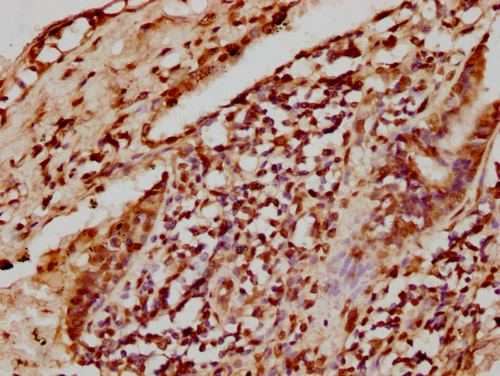

IHC (Immunohistochemistry)

(IHC image of diluted at 1:8 and staining in paraffin-embedded human liver cancer performed on a Leica BondTM system. After dewaxing and hydration, antigen retrieval was mediated by high pressure in a citrate buffer (pH 6.0). Section was blocked with 10% normal goat serum 30min at RT. Then primary antibody (1% BSA) was incubated at 4 degree C overnight. The primary is detected by a biotinylated secondary antibody and visualized using an HRP conjugated SP system.)